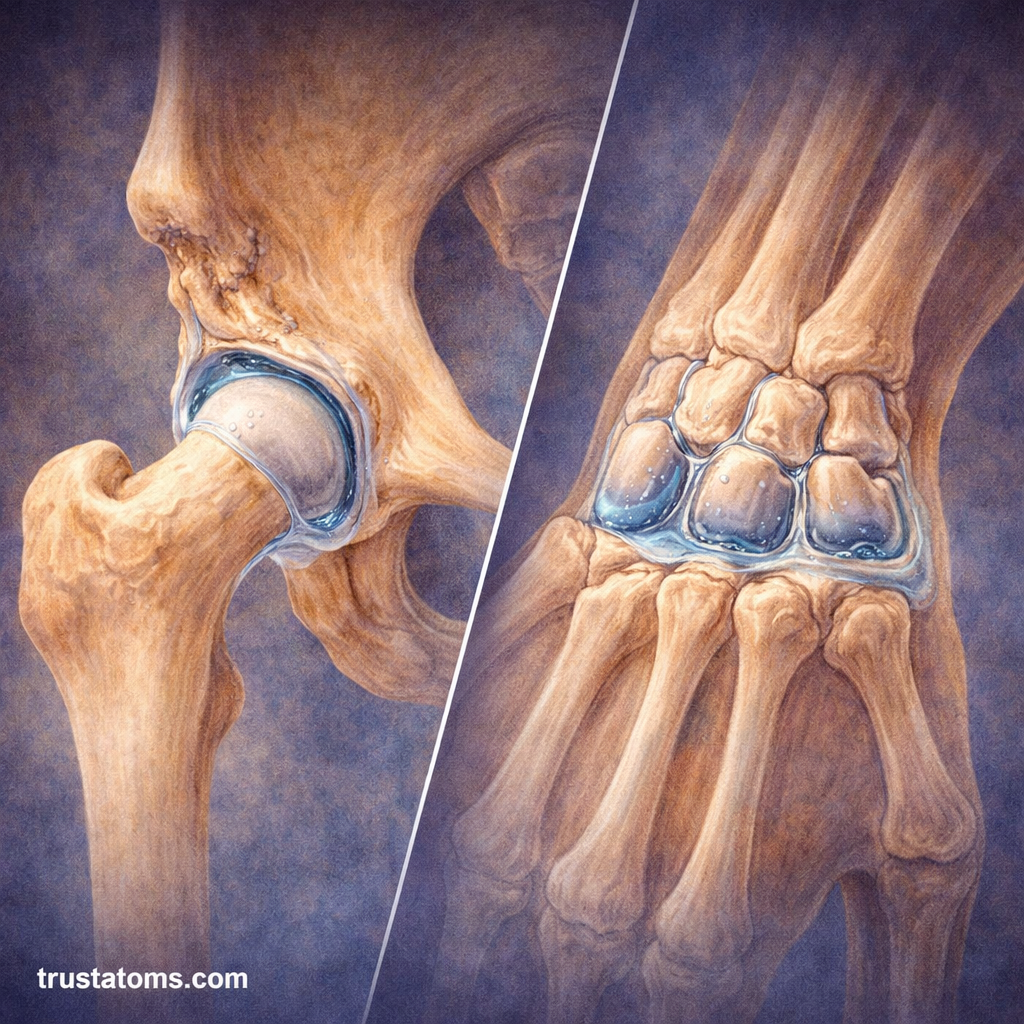

Common Examples

- Knee

- Shoulder

- Hip

- Elbow

- Wrist

Key Features of Synovial Joints

- Joint cavity filled with synovial fluid

- Articular cartilage covering bone ends

- Synovial membrane lining the joint

- Joint capsule enclosing the structure

- Ligaments providing stability

These components work together to enable smooth and efficient movement.

Structure of a Synovial Joint

Each part of a synovial joint has a specific role in reducing friction and maintaining joint integrity.